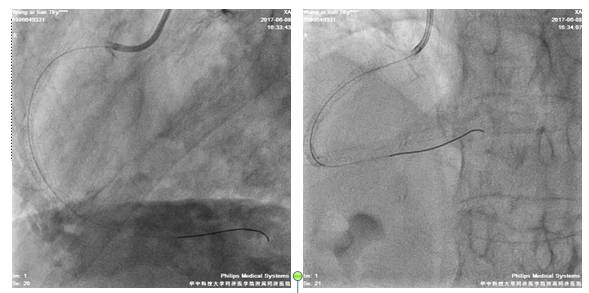

术后造影

四日后,尝试左冠PCI术

股动脉路径

7F EBU3.5/GC

Runthrough NS,ASAHI SION,BMW导丝

2.5*20mm球囊扩张LAD10*12atm

先后与LAD远段-近段置入2.5*33mm、2.75*33mm、3.0*29mm DES支架,三支架串联